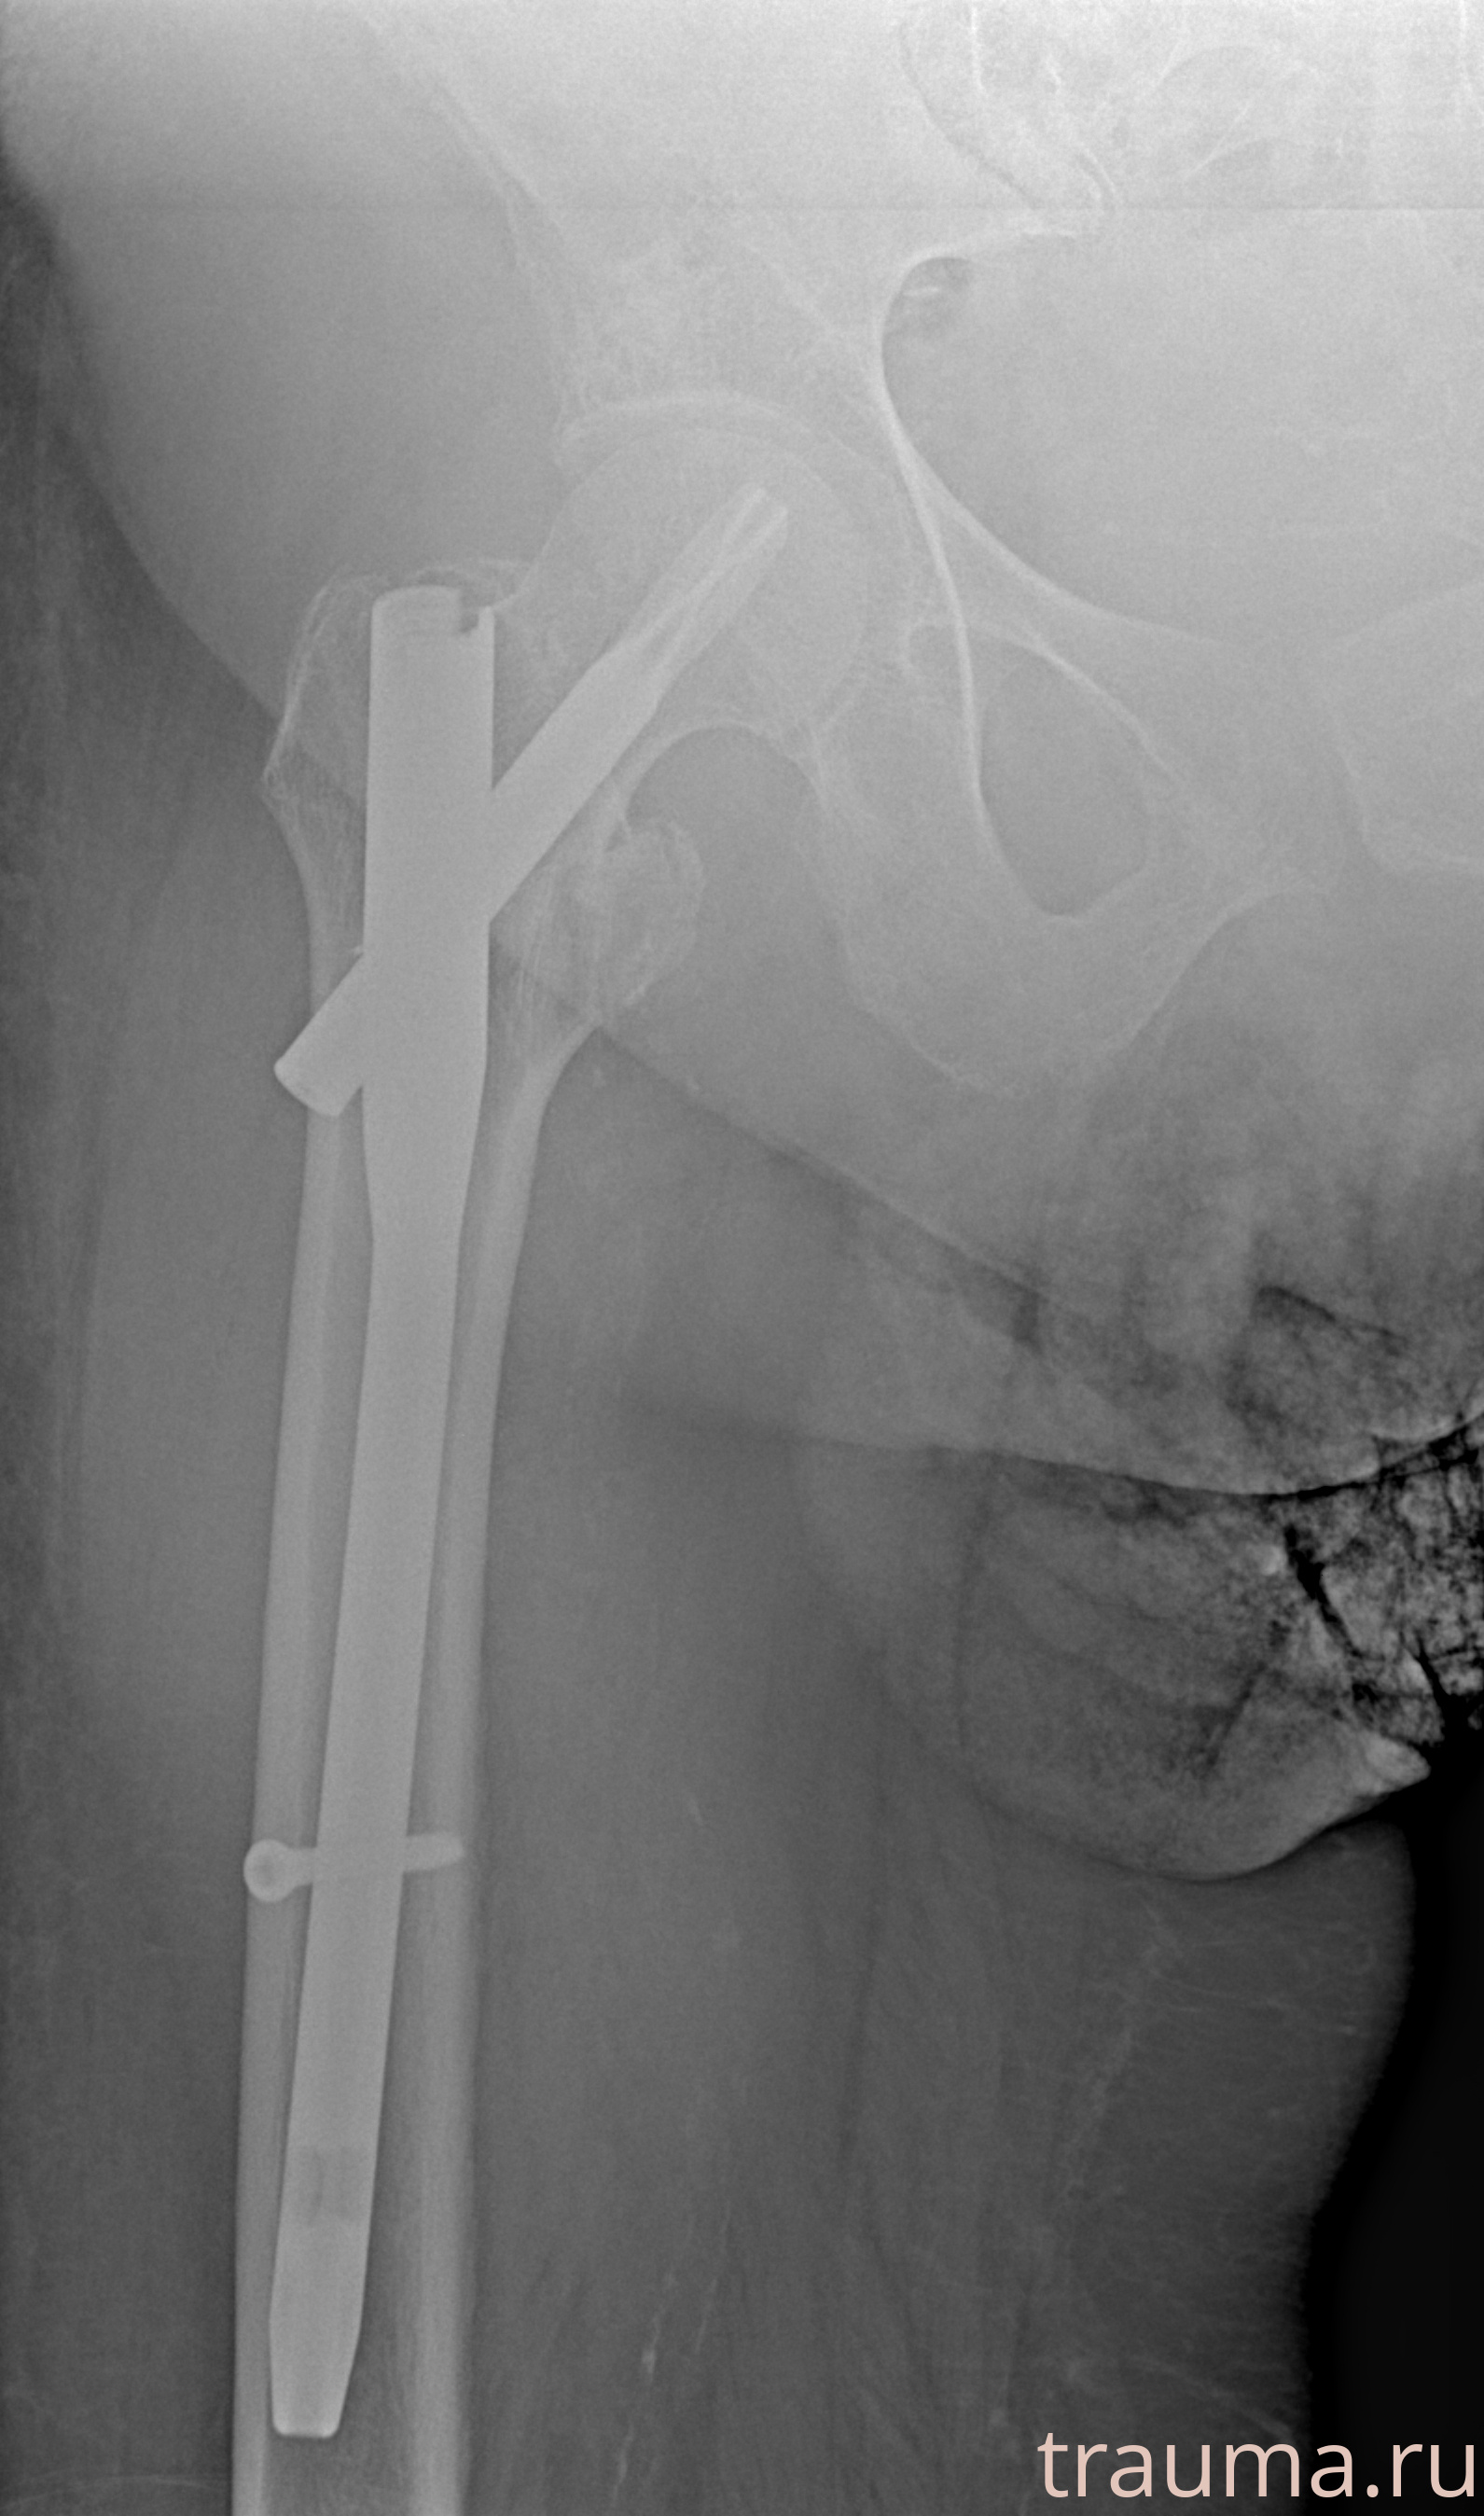

Рентгенограммы